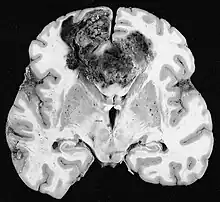

Le lymphome primitif du système nerveux central représente environ 2 pour cent à 3 pour cent de toutes les tumeurs cérébrales chez les patients ayant un système immunitaire normal. Ils surviennent plus fréquemment chez les hommes de plus de 55 ans jusqu'à 60 ans. Près de la moitié de tous les lymphomes surviennent chez des patients de plus de 60 ans et environ un quart chez des patients de plus de 70 ans. L'incidence semble augmenter avec l'âge, mais la raison n'est pas encore claire. Les patients dont le système immunitaire est affaibli sont plus à risque de développer un lymphome du SNC, de sorte que ceux qui ont subi une greffe d'organe ont une immunodéficience congénitale ou une maladie auto-immune, ou sont infectés par le virus de l'immunodéficience humaine. Les lymphomes cérébraux associés au VIH sont associés au virus d'Epstein-Barr, en particulier chez les patients dont le nombre de lymphocytes CD4 est inférieur à 500 cellules par millimètre cube dans le sang. La plupart des lymphomes du SNC sont des lymphomes diffus à grandes cellules B.

Les patients souffrent d'une variété de symptômes caractéristiques d'une lésion massive focale ou multifocale. L'IRM montre généralement des tumeurs avec un rehaussement de contraste homogène au sein de la substance blanche périventriculaire profonde. La multifocalité et le rehaussement inhomogène sont typiques des patients dont le système immunitaire est affaibli. L'analyse du lymphome du SNC est extrêmement importante dans le diagnostic différentiel de la néoplasie cérébrale. Il est à noter que l'administration de corticoïdes peut entraîner la disparition complète du rehaussement, rendant difficile le diagnostic des lésions. Par conséquent, si un lymphome du SNC doit être pris en compte dans le diagnostic différentiel, les corticoïdes doivent être évités à moins que l'effet de masse ne provoque un problème grave et immédiat chez le patient.

La biopsie de la lésion suspectée est cruciale. Contrairement au lymphome systémique à grandes cellules B, dans lequel la chimiothérapie et la radiothérapie sont efficaces et le traitement des lésions localisées est curatif, le lymphome du système nerveux central répond généralement au traitement initial mais réapparaît ensuite. Comme pour le lymphome systémique, le rôle de la chirurgie est principalement limité à l'obtention d'échantillons de tissus appropriés pour le diagnostic.

Dans le passé, la radiothérapie était administrée à l'ensemble du cerveau (panencéphalique). La médiane de survie est d'environ 12 même avec des lésions localisées Mois. La récidive affecte généralement le site de la blessure précédente ainsi que d'autres régions. Les réponses à la chimiothérapie sont plus prometteuses. Les essais cliniques dans lesquels le méthotrexate à haute dose seul a été utilisé comme premier traitement et la radiothérapie a été retardée jusqu'au moment de la rechute ou de la progression ont montré une meilleure survie globale que la radiothérapie seule. Encore plus efficace était la combinaison de méthotrexate, vincristine, procarbazine, méthotrexate intrathécal, cytarabine et radiothérapie panencéphalique et cytarabine, ou l'utilisation d'une chimiothérapie intra-artérielle avec méthotrexate intra-artériel, cyclophosphamide injecté par voie intraveineuse et étoposide après modification du sang. barrière cérébrale avec du mannitol. La médiane de survie sous méthotrexate était de 24 jusqu'à 40 mois beaucoup plus élevé qu'avec la radiothérapie seule (extrêmes 24 jusqu'à 40 mois). Dans certains cas, la radiothérapie n'est utilisée que pour les rechutes lorsqu'il y a une régression initiale avec la chimiothérapie. Des cas de survie longue ont également été rapportés sans radiothérapie.